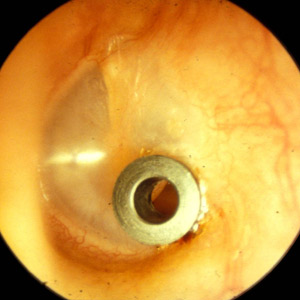

Die Therapie der Wahl bei der chronischen Mittelohrentzündung ist eine Operation des Mittelohres, bei welcher die Gehörknöchelchen rekonstruiert, das Trommelfell wieder in der richtigen Position repariert und verstärkt wird und die Belüftung des Ohres verbessert wird. Bei der serösen Mittelohrentzündung kann die Belüftung durch die zeitlich begrenzte Einlage von Drainageröhrchen (Paukenröhrchen) wieder hergestellt werden. Bringt dies keinen langfristigen Erfolg, besteht heute die Möglichkeit mit einem Ballon in einer kurzen Operation die Ohrtrompete zu weiten und dadurch die Belüftung zu verbessern (Tubenballondilatation).

Paukenröhrchen